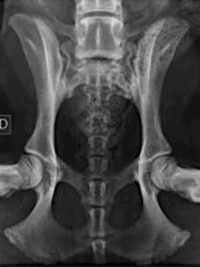

Le displasie possono essere diagnosticate precocemente con esami radiografici eseguiti dal quinto/sesto mese di vita. Questi esami, effettuati in sedazione, includono proiezioni specifiche per anca e gomito e sono essenziali per intervenire tempestivamente.

Nello specifico lo studio dell’anca prevede ben 4 proiezioni (antero posteriore standard, in distrazione, a rana e dar).